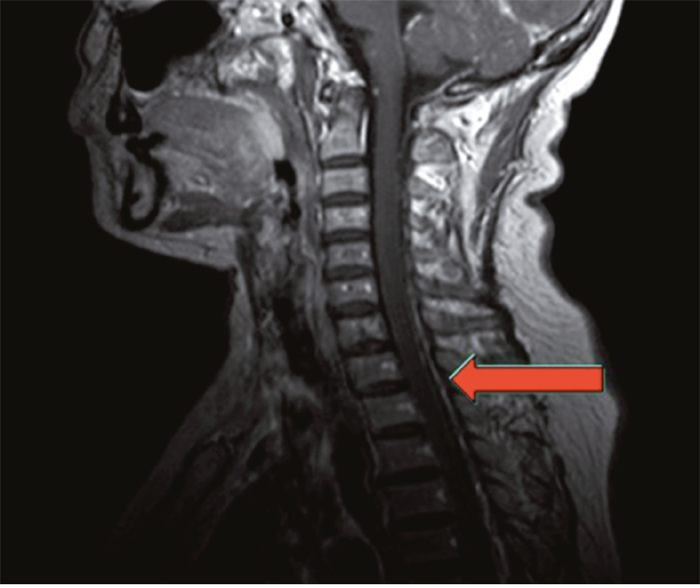

Figure 2: Magnetic resonance image of the same patient. The image showed metastasis of spinal dura mater, which meant a failure in maintenance treatment and demand for shift of therapeutic regimen.